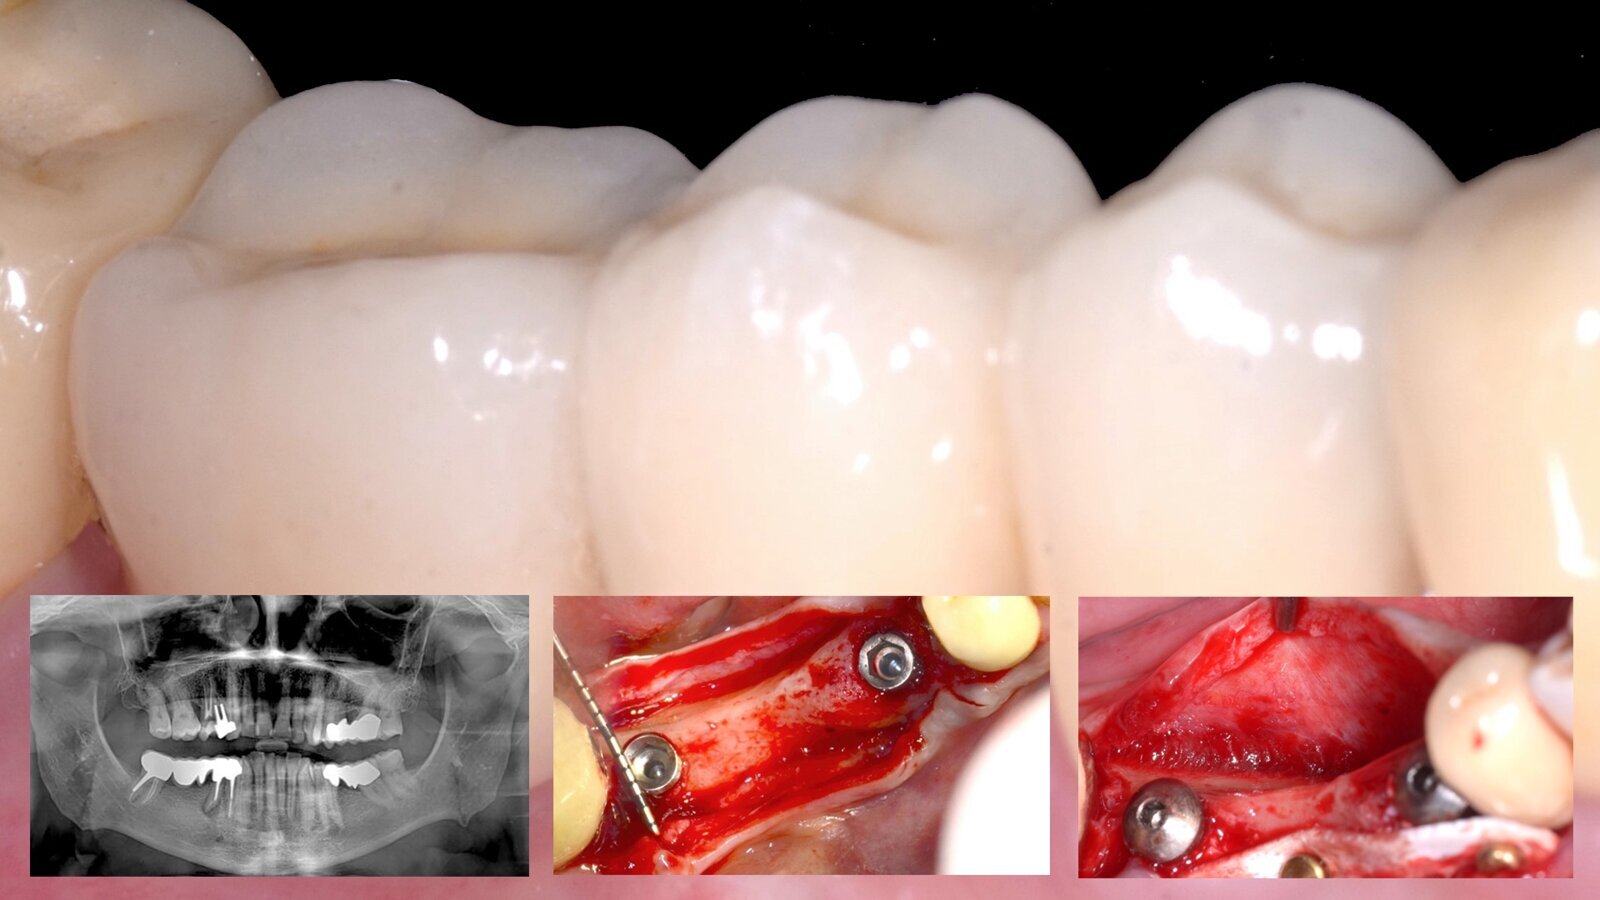

El resultado final de la rehabilitación inmediata con implantes y ROG horizontal (imagen principal) y varios de los pasos clínicos realizados por el Dr. Terry Zaniol (imágenes inferiores) para obtener un resultado estético en una paciente con pronunciado déficit óseo.

Este artículo presenta el caso clínico de una mujer de 58 años que precisó la rehabilitación inmediata de implantes dentales en las posiciones 44 y 46. Tras la evaluación clínica y radiográfica, se observó un déficit óseo horizontal en la zona a rehabilitar. Por lo tanto, se realizó una Regeneración Ósea Guiada horizontal y la colocación simultánea de implantes en las posiciones 44 y 46. La cirugía regenerativa se realizó con un injerto heterólogo de colágeno preservado de origen equino protegido por una lámina de hueso cortical flexible de 0,5 mm de grosor.

Caso clínico de una mujer de 58 años de edad, en buen estado de salud, que acudió al cirujano para solicitar una rehabilitación implantológica a raíz de la excesiva movilidad y migración apical del puente metal-cerámico en los dientes 44-46. Tras la investigación clínica y radiográfica (Fig. 1), se observó un déficit óseo horizontal. Por lo tanto, se realizó un ROG horizontal y la colocación simultánea de implantes en las posiciones 44 y 46.

Fig. 1. Ortopantomografía inicial: se observa un puente metal-cerámico en las posiciones 44-45-46 con movilidad del pilar.